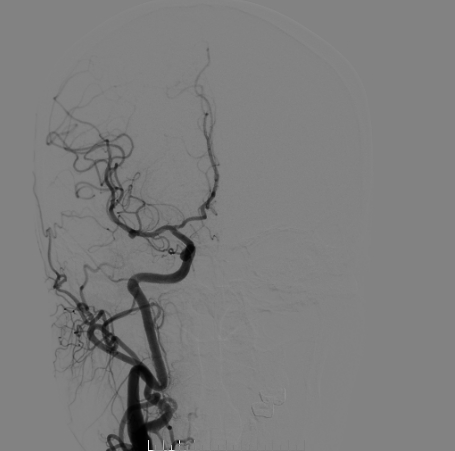

右侧颈总造影:右侧大脑中动脉瘤

右侧大脑中动脉瘤,瘤颈处发出颞支,颈宽3.79mm,瘤高3.51mm,远近端载瘤动脉直径分别为2.43mm、2.52mm。